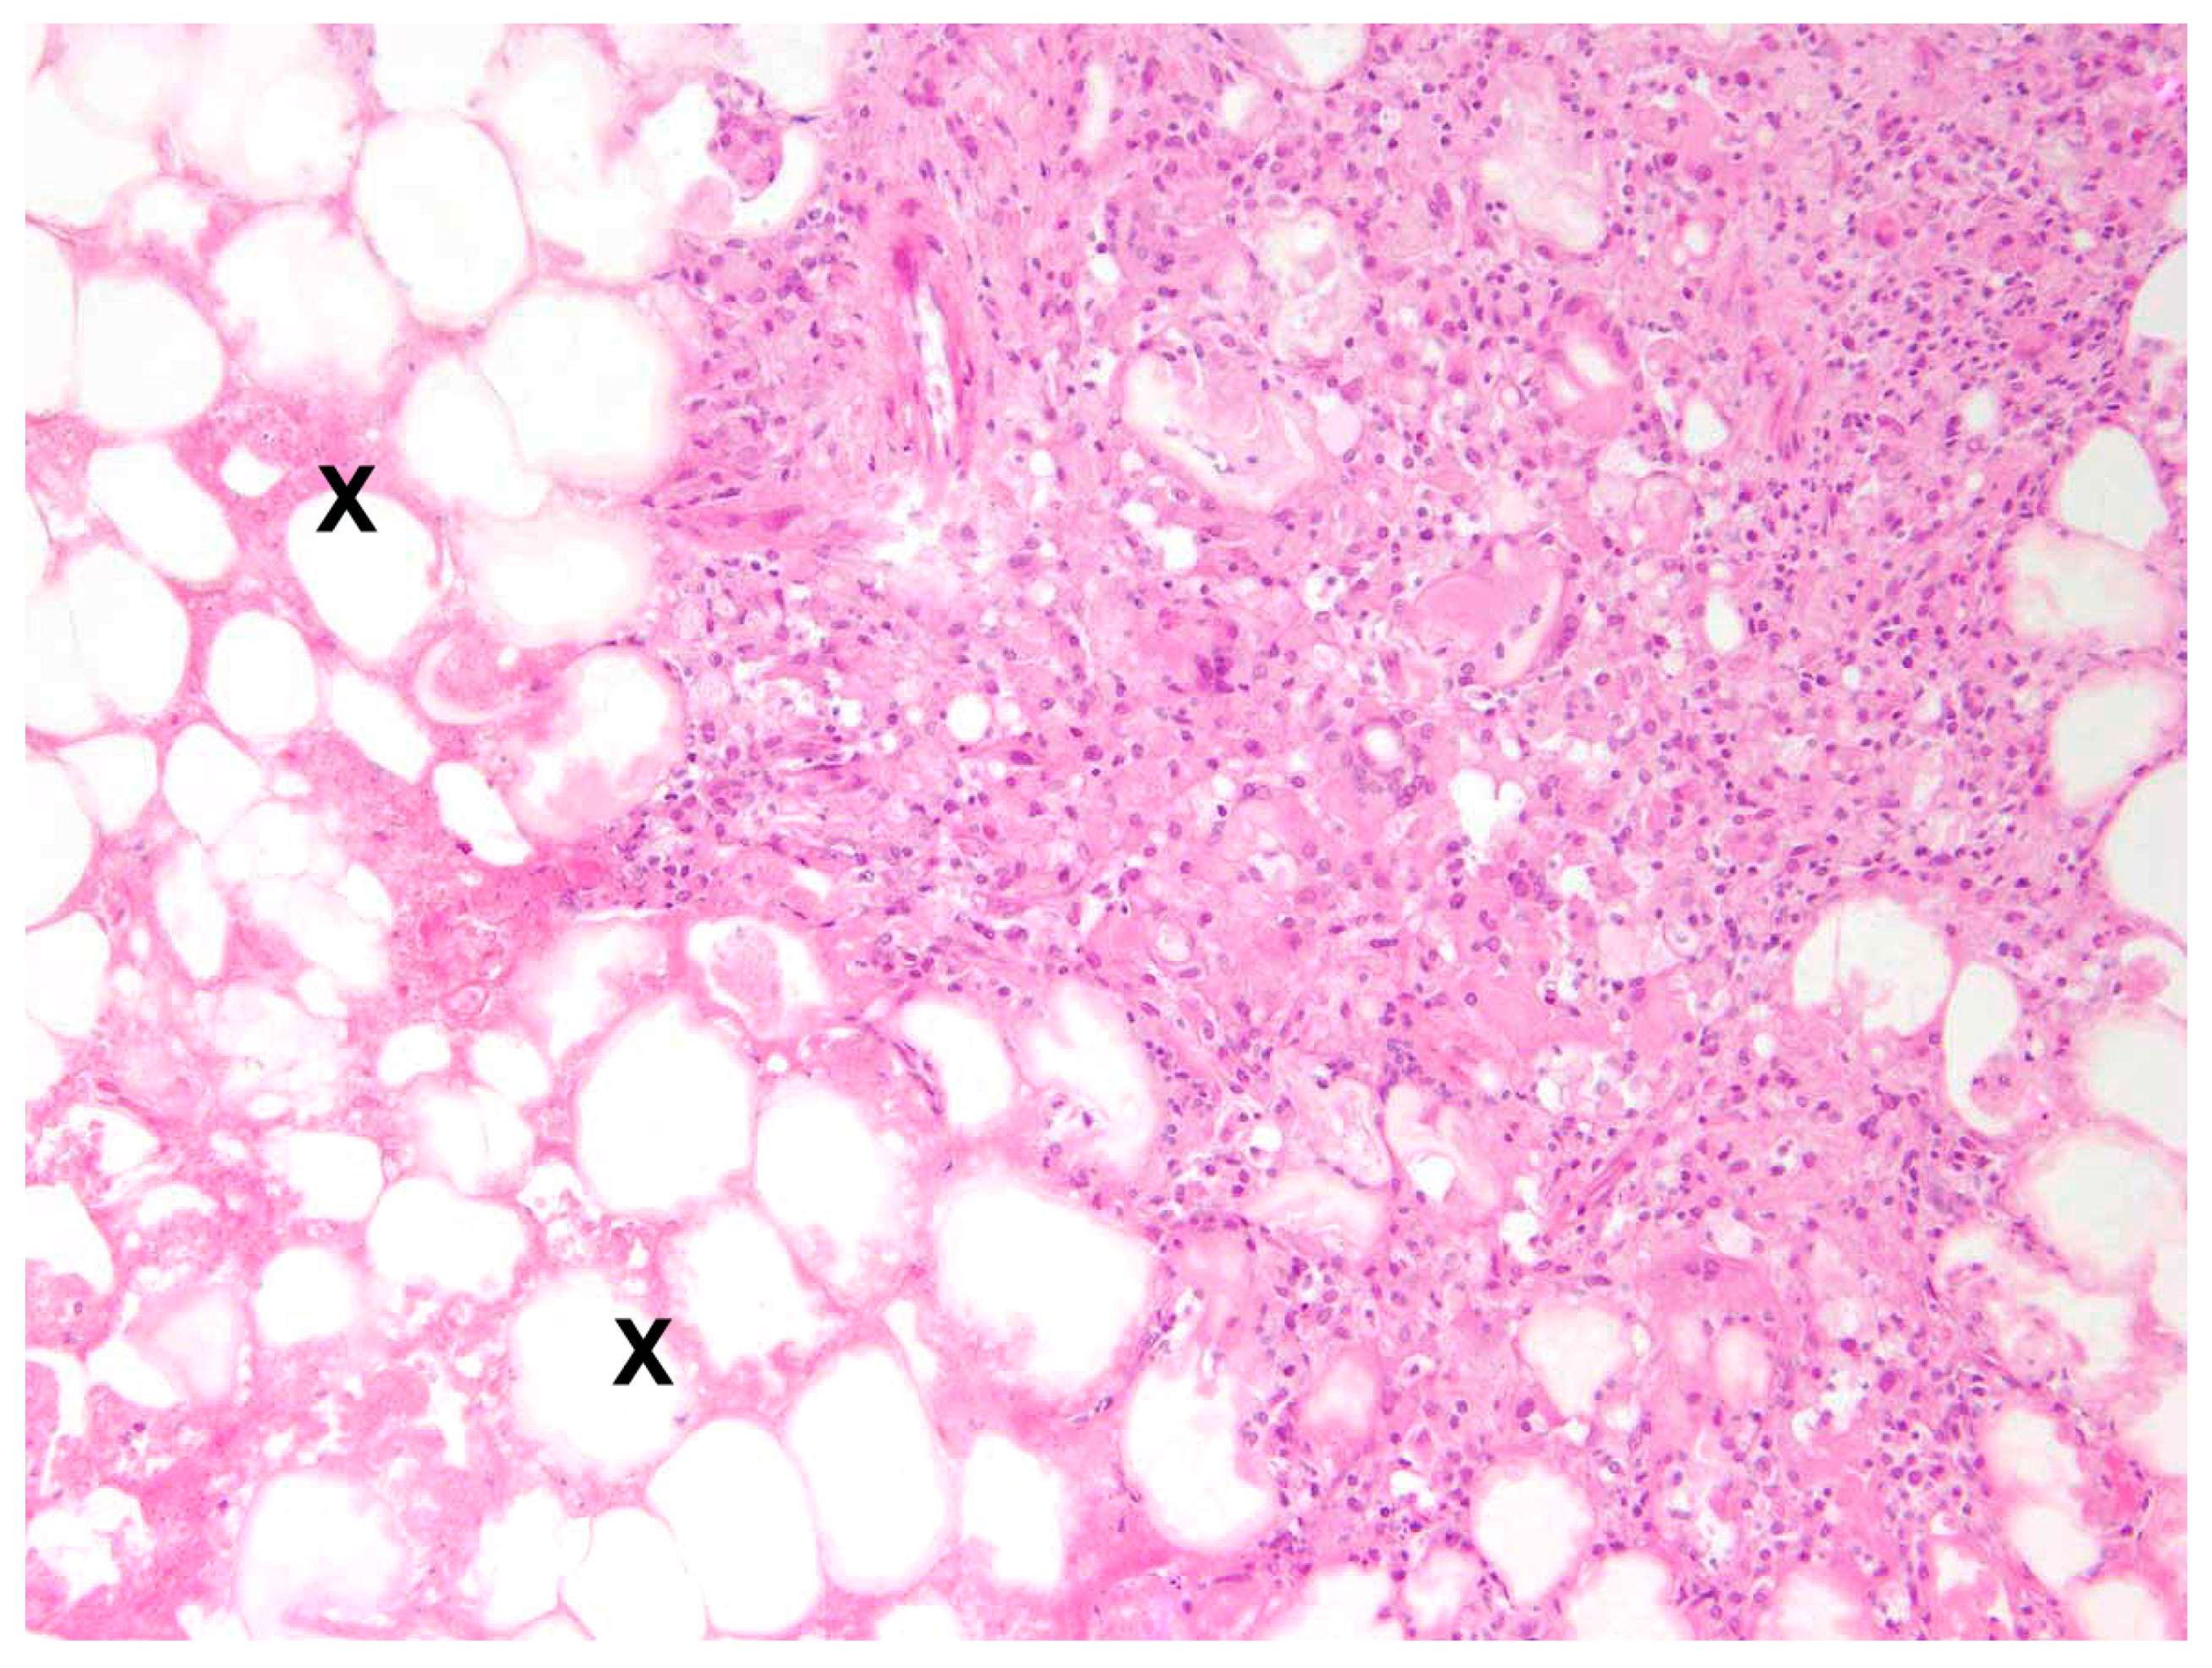

The main type of hepatitis was non-purulent with different proportions of lymphocytes, plasma cells, and macrophages (93.0%, n = 80;

Figure 4), followed by purulent (14.0%, n = 12), necrotising (5.8%, n = 5), and granulomatous type (5.8%, n = 5). Eight cases (9.3%) of hepatitis showed a mixed inflammatory type.

In 81.0% of cases, the enteritis was non-purulent (n = 17) with various infiltrations of lymphocytes, plasma cells, histiocytes, and partly eosinophils (

Figure 8), and in 33.3%, a granulomatous (n = 7) inflammatory type was present. A mixed inflammatory type was detected in 14.3% (n = 3) of affected animals.